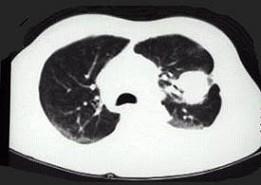

问题 女,68岁,咳嗽伴胸痛胸闷一月,CT检查如图,最可能的诊断为 ( )

选项 A、左上肺软骨肉瘤伴胸膜转移 B、左上肺结核 C、左上肺周围型肺癌伴胸膜转移 D、左上肺血管瘤 E、左上肺不张

答案 C